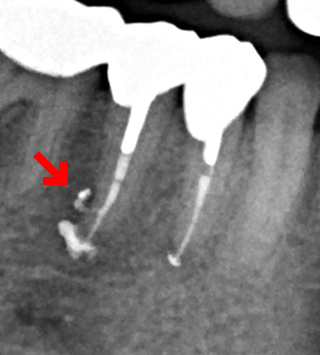

- 右下の歯にうずくような痛みがあると来院。レントゲンで大きな歯根嚢胞を確認。

右下5番は根管に側枝という横穴が開いてそのせいでその部分にも嚢胞がありました。一般的な側方加圧充填ではこの部分は充填剤が入らないため抜歯になってしまうケースです。

根管治療を4回行い症状がなくなったため根管充填を行いました。

垂直加圧根管充填できちっと根尖にも側枝にも充填剤が入りました。側枝に充塡剤がしっかり入っているとこのようにレントゲンに写ります(部分)。処置後3年経過しましたが快適だそうです。